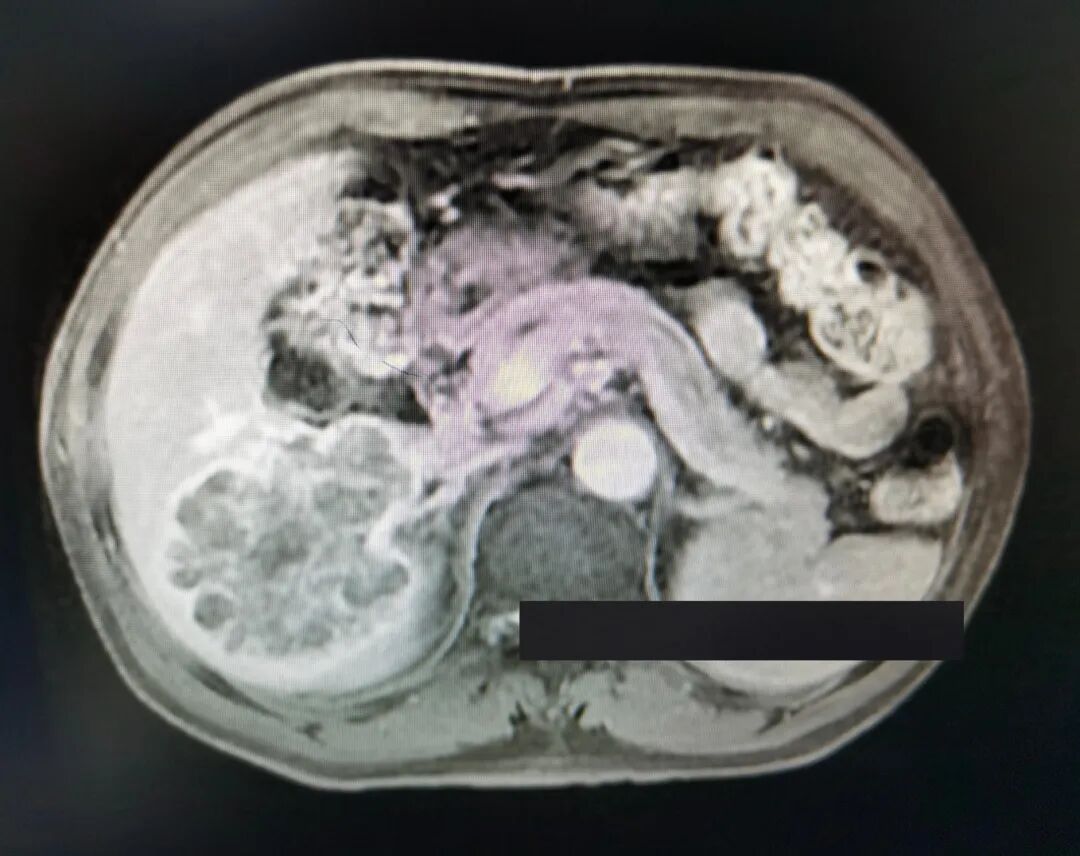

予以酪氨酸激酶抑制剂(TKI) PD-1免疫检查点抑制剂治疗计3个月,其间行两次TACE介入治疗。复查甲胎蛋白下降至26 ng/ml,增强核磁影像提示病灶坏死、缩小、部分子灶消失,较大者位于右后叶右尾状叶,大小12×9 cm,仍见残留多发活性(影像如图2所示)。

图2.转化后核磁影像(滑动浏览)